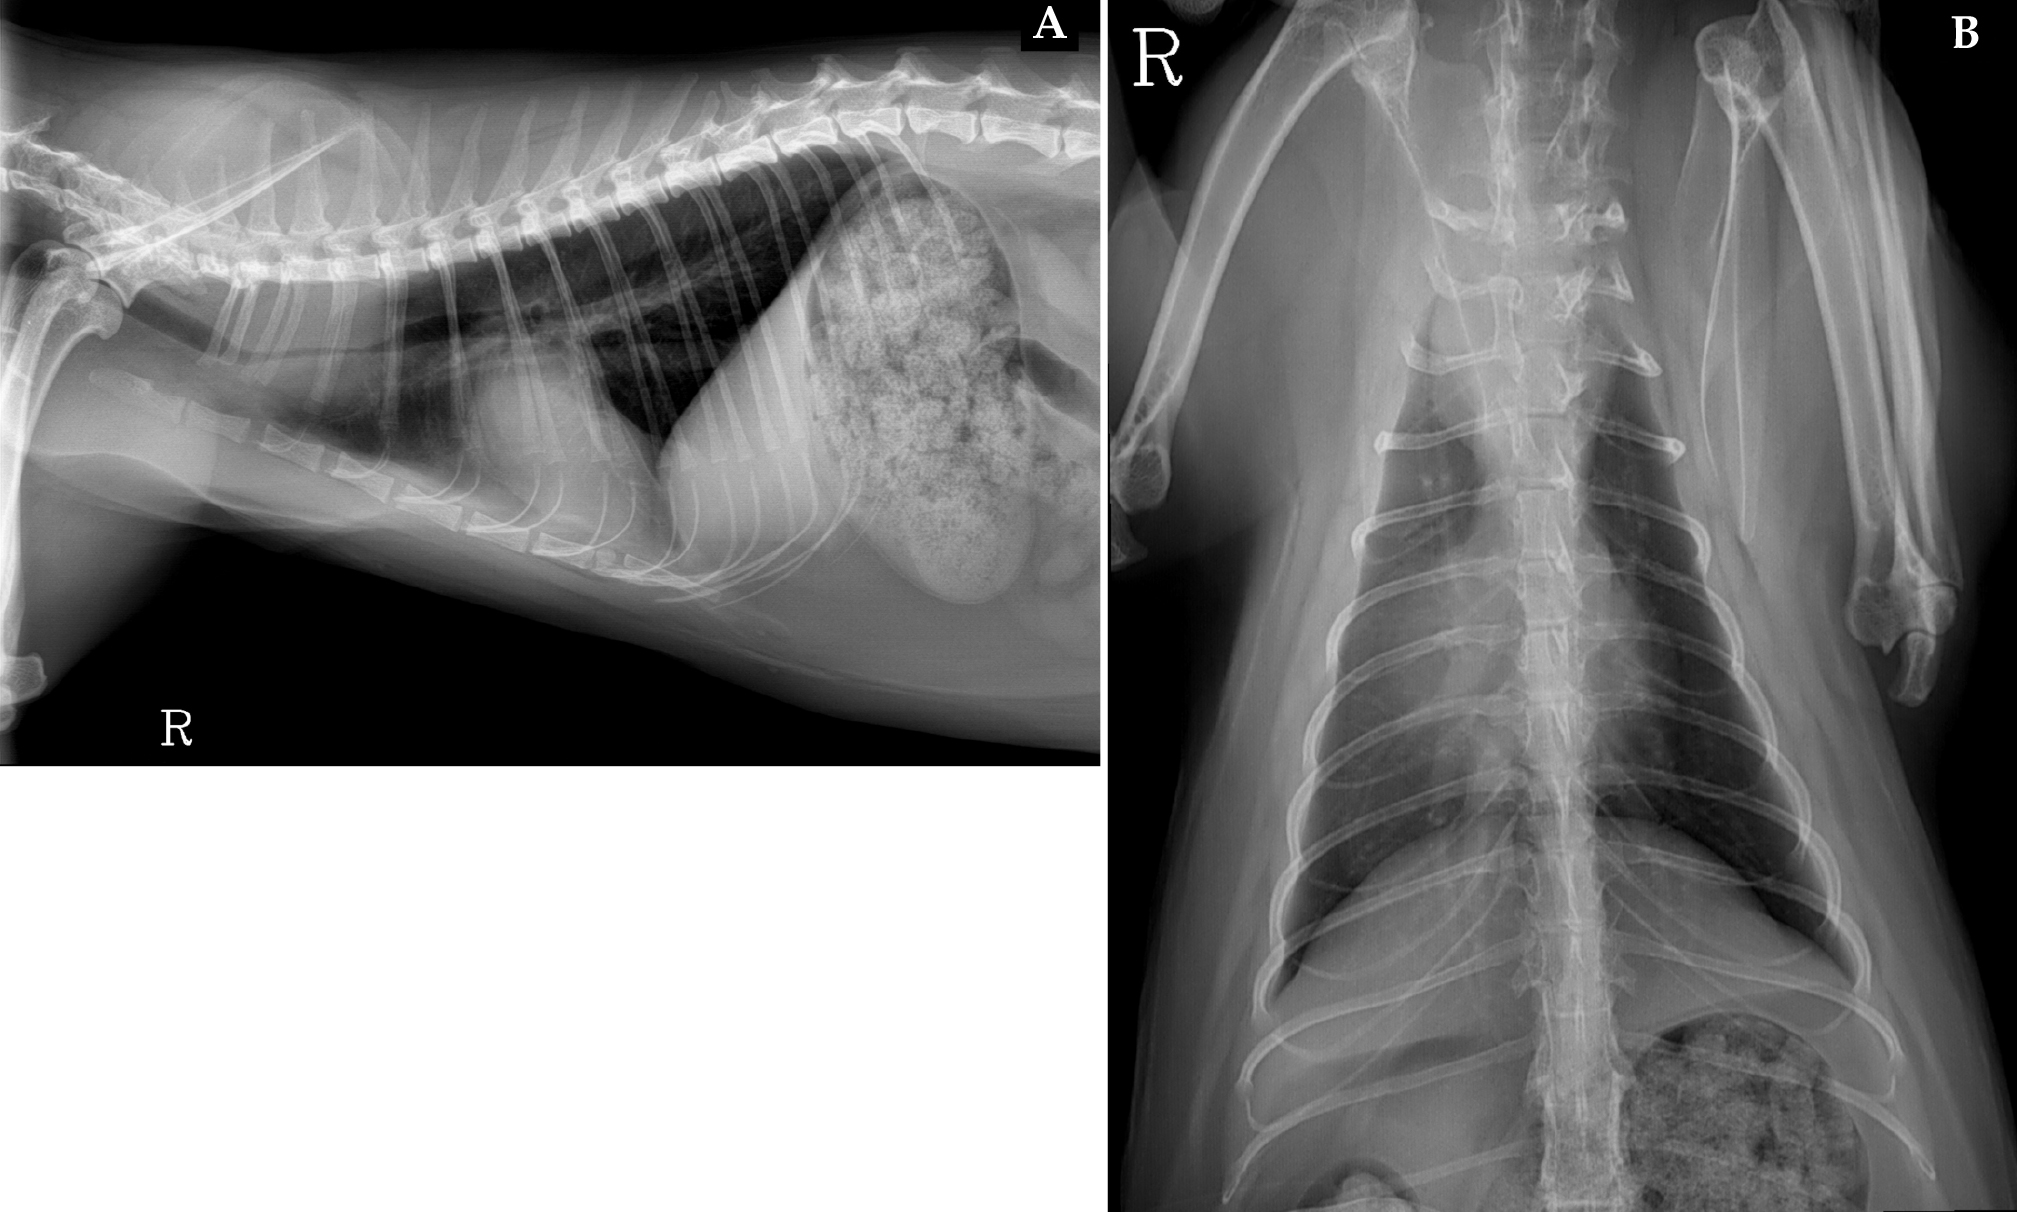

Se realizó un estudio radiográfico del tórax en proyecciones lateral derecha y dorsoventral (Fig. 1).

Radiografías de tórax de una gata hembra de 4 años. (A) Proyección lateral derecha. (B) Proyección dorsoventral.